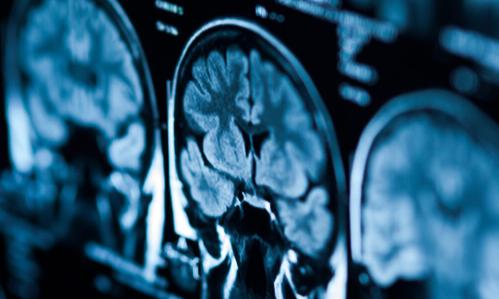

A new, more rapid form of transcranial magnetic stimulation holds promise for treating #depression. TWEET